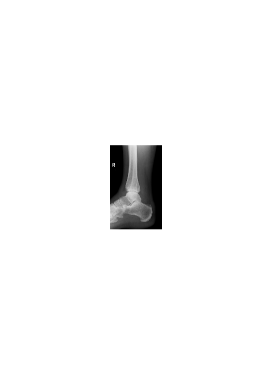

We illustrate now the suitability of the proposed mixed dictionary to produce high quality approximations of the set of X-ray medical images shown in Fig. 3. This set of twenty images is the Lukas 2D 8 bit medical image corpus, available on [33].

Image PSNR DWT DCT OMP2D HBW Hand1 48.1 30.0 26.4 39.0 72.6 Foot1 48.6 26.6 26.1 30.4 44.9 Foot0 48.6 25.5 26.1 42.7 65.2 Head0 47.4 25.3 24.3 51.9 63.2 Knee1 48.0 22.7 23.0 34.5 59.8 Sinus0 47.1 18.9 18.7 31.3 46.7 Hand0 48.8 18.6 18.7 32.2 47.9 Head1 46.4 17.5 15.1 38.3 44.4 Knee0 49.1 17.4 17.5 33.2 45.9 Sinus1 45.8 17.2 17.1 29.5 43.0 Breast0 44.3 15.7 15.3 36.7 41.0 Breast1 44.3 11.5 11.2 27.7 29.7 Thorax0 44.1 10.6 10.9 25.1 27.4 Thorax1 43.4 10.3 9.6 25.4 26.3 Leg0 48.9 8.2 8.4 21.2 22.3 Leg1 49.2 5.8 5.9 15.1 15.4 Pelvis1 44.3 4.8 4.7 12.3 12.6 Pelvis0 44.4 4.6 4.7 12.4 12.6 Spine1 47.0 3.5 3.6 9.3 9.4 Spine0 47.4 2.9 2.8 7.1 7.7